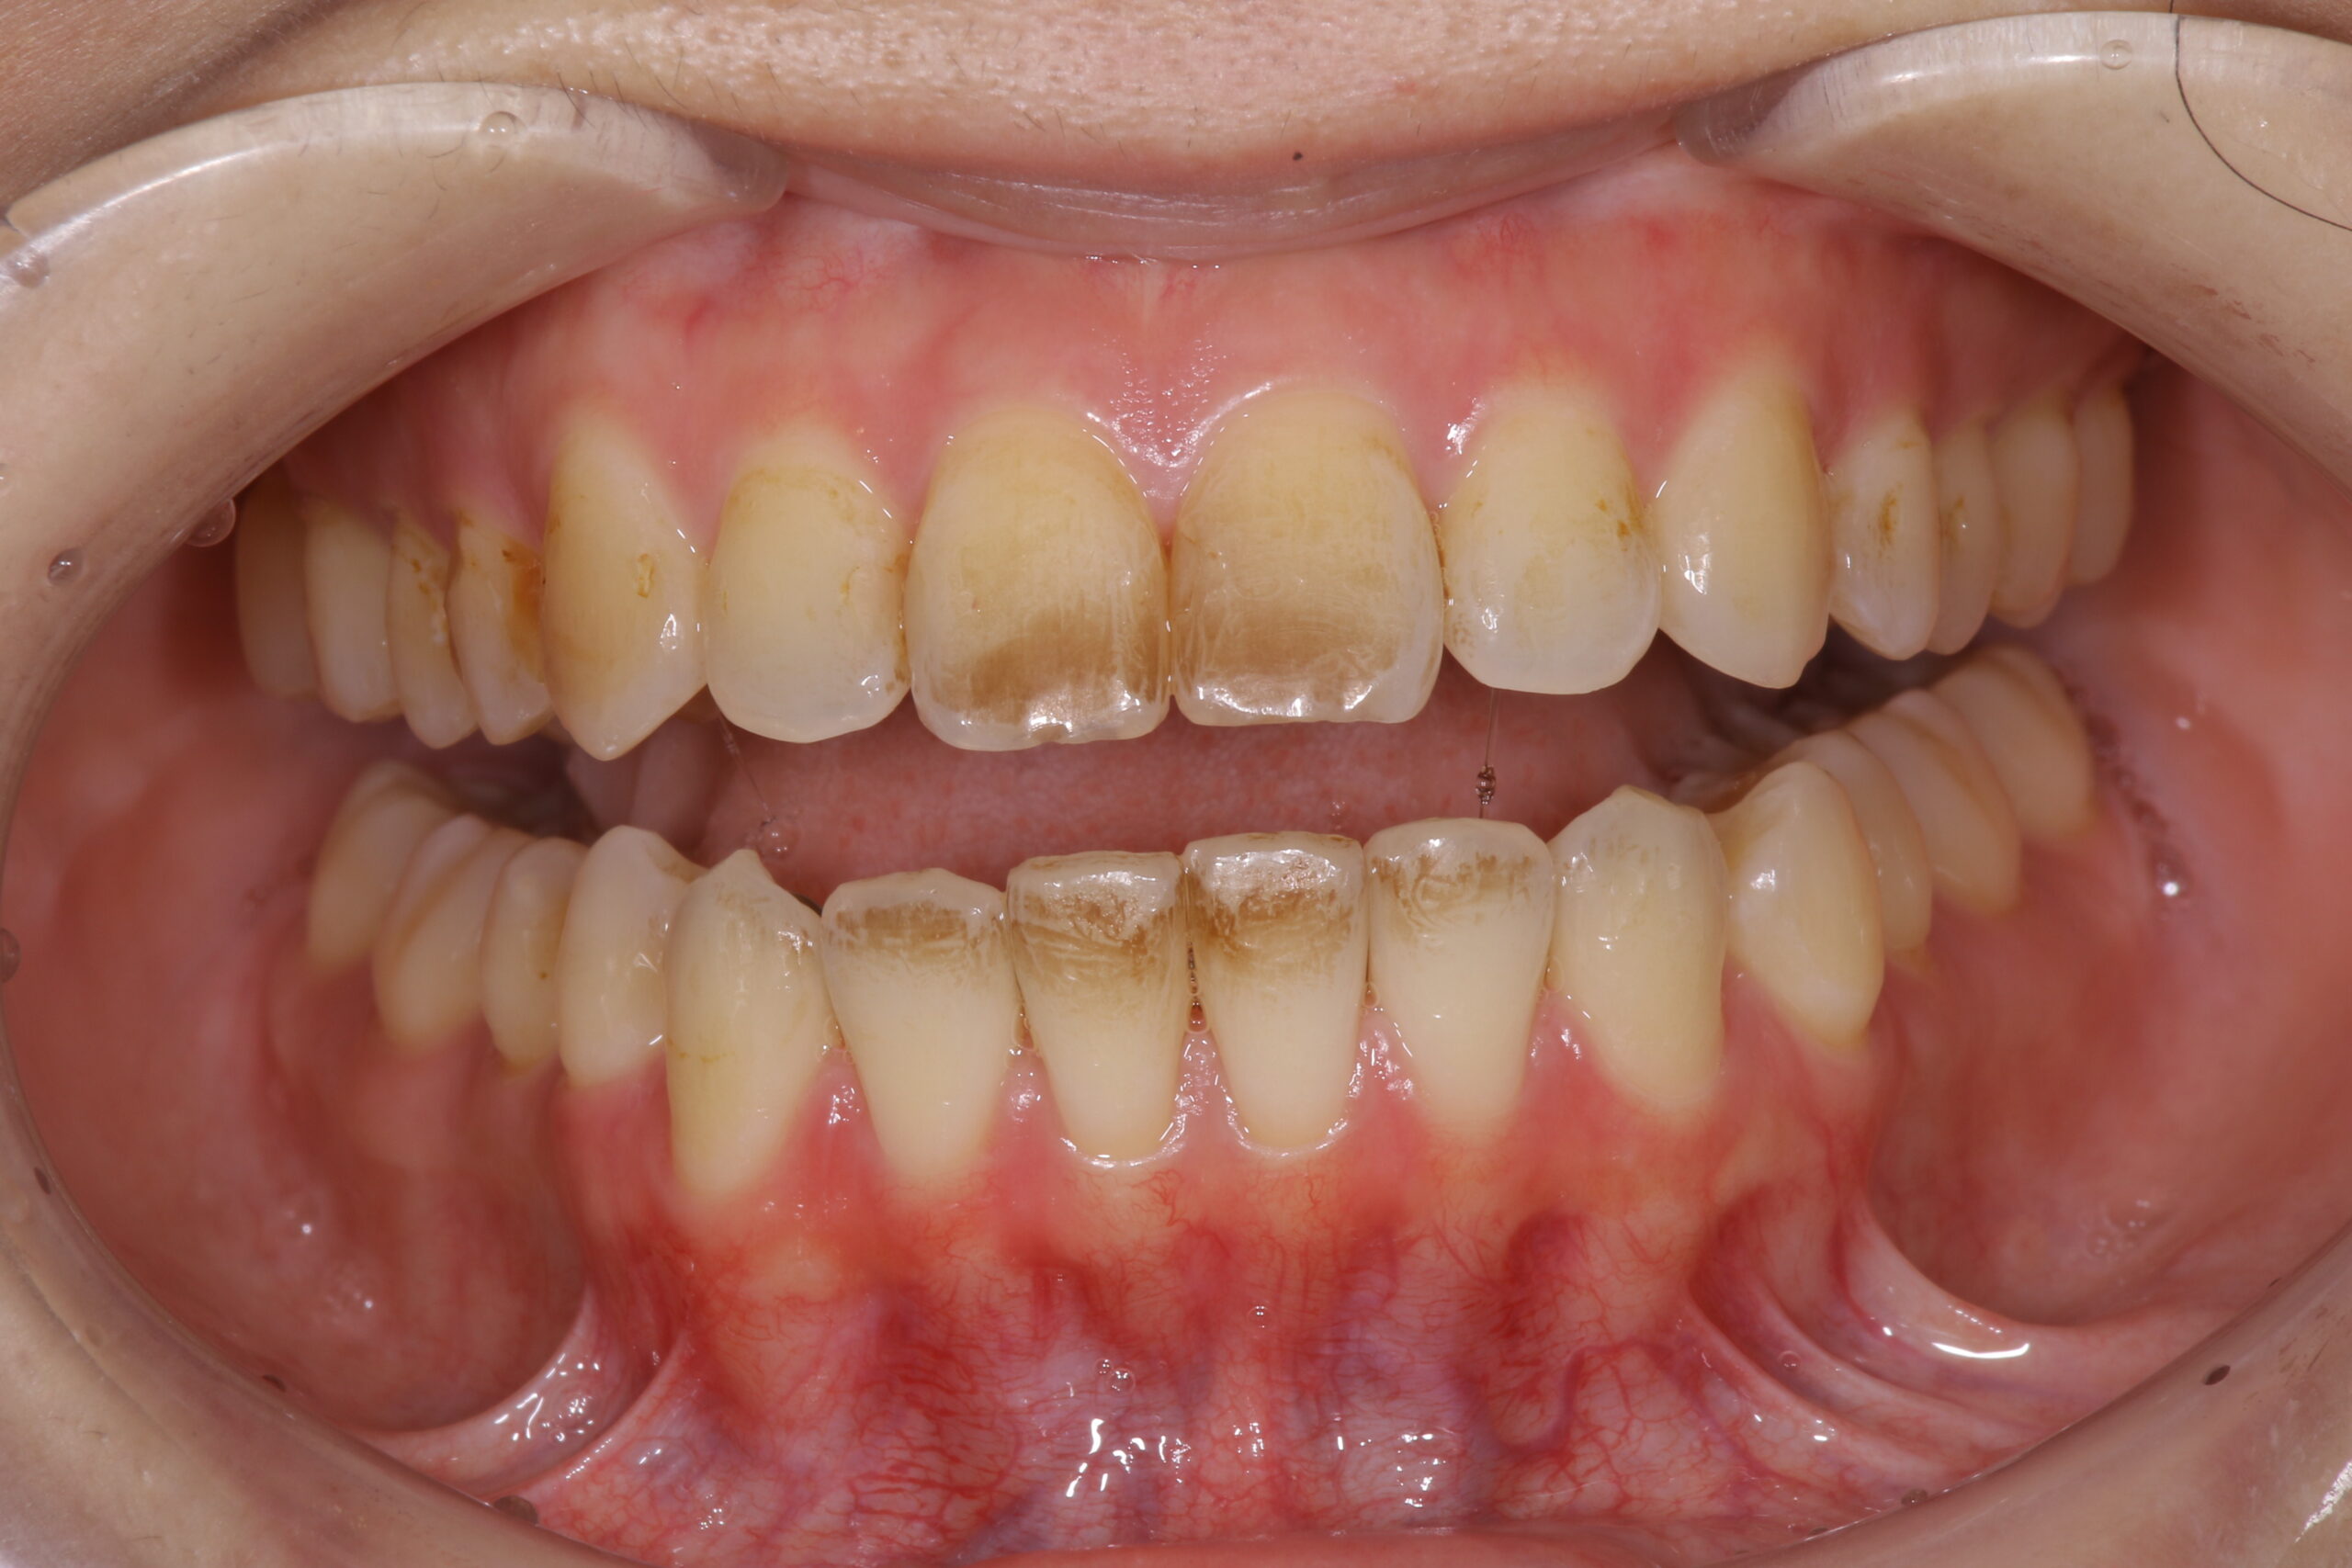

【口の乾燥により汚れや着色が残りやすい】

口が開いて歯が乾燥したところに着色の強い飲食が付くことによって歯(特に上下前歯)に着色が付きやすくなります。